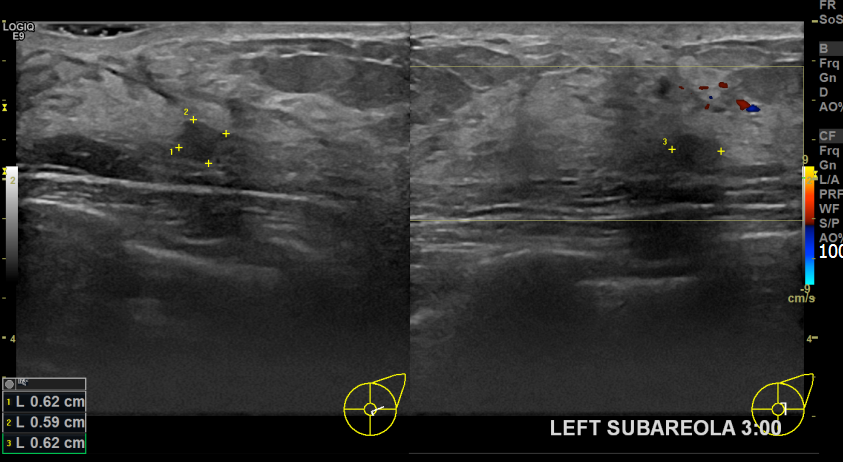

상기환자 유방 경과관찰중인 50대 여성분으로 좌측 새로생긴 혹  조직검사시행후 침윤성유방암으로 진단되셨습니다.